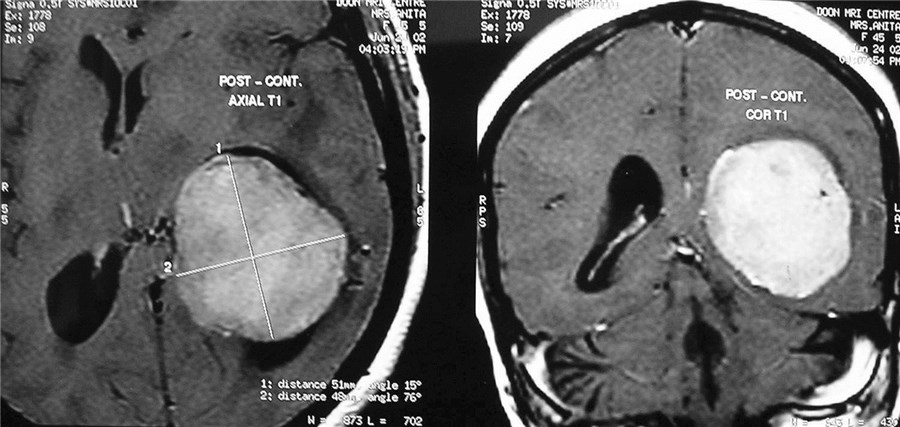

Intracranial Meningiomas

Meningiomas are solid, nodular (rarely, cystic), benign tumors that arise from the coverings of the brain, and compress the adjacent brain tissue. Usually present with headache, visual disturbances or weakness of half of the body. Diagnosis is by progression, especially if the tumor removal has been incomplete. Diagnosis is by MRI and surgery is curative.